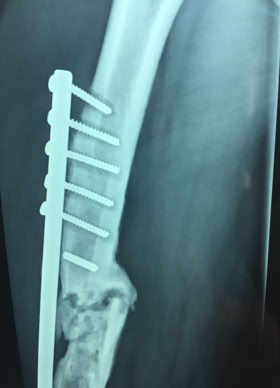

Traumatología

El coste de una intervención quirúrgica de cirugía menor con ingreso

Coste del material de Osteósíntesis para una fractura de fémur

El coste de una intervención quirúrgica de alta complejidad

Gracias a COEM es posible realizar una traumatología del siglo XXI en una comunidad que de otra forma solo tendría acceso a una medicina medieval